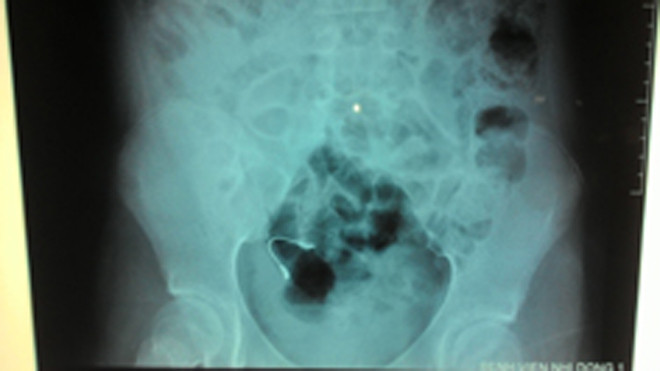

Cọng kẽm niềng răng mà bệnh nhi nuốt vào bụng. Ảnh: BV cung cấp

Sau khi kiểm tra X-quang, các bác sĩ phát hiện có dị vật ở đường tiêu hóa nên cho bệnh nhi uống thuốc nhuận tràng và theo dõi. 3 ngày sau, bé A. tự đi tiêu ra dị vật, tình trạng sức khỏe trở lại bình thường, không đau bụng, ăn uống tốt và đã được xuất viện.